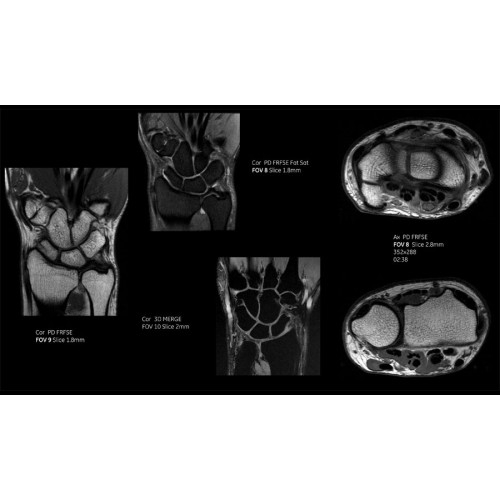

- Технология Digital Surround Technology (DST) — это новая технология объемной оцифровки данных, объединяющая сигналы от каждого элемента катушки. Прекрасное соотношение сигнал/шум и чувствительность поверхностных катушек в сочетании с превосходной однородностью и высокой проникающей способностью встроенной радиочастотной катушки — все это позволяет создавать качественные изображения не только позвоночника, но и всего тела.